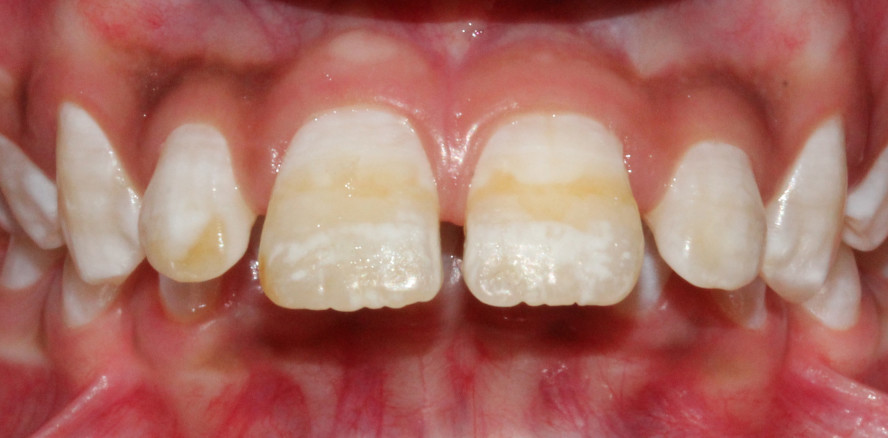

Dass Fluorid die Zähne stärkt und vor Karies schützt, daran besteht kein Zweifel. Allerdings entscheidet tatsächlich die Menge darüber, ob eine Stärkung oder Schwächung des Zahnschmelzes (Fluorose) stattfindet. Letztgenanntes kann sich durch Verfärbung der Zähne, undurchsichtige weiße Flecken oder Linien äußern – ein weltweit verbreitetes Problem im Kindesalter.

Forscher des NYU College of Dentistry, USA, haben anhand einer Untersuchung molekularer Mechanismen herausgefunden, wie dies konkret zustande kommt. Sie erkannten, dass eine Überdosierung mit Fluorid zu einer fehlerhaften Mineralisierung des Zahnschmelzes führt. Grund hierfür ist eine Störung des Kalziumhaushalts der Ameloblasten (schmelzbildende Zellen), die infolgedessen weniger Kalziumeinlagerungen vornehmen. Auf diese Weise wird die Funktion der Mitochondrien, der Stromerzeuger der Zellen, ebenfalls beeinflusst. Die Zellen geraten schlussendlich unter dem „Fluoridbeschuss“ in Stress, der eine adäquate Kalziumverarbeitung verhindert. Die Mineralisierung des Zahnschmelzes entwickelt sich damit fehlerhaft und es entstehen die typischen Verfärbungen im Zahnschmelz.